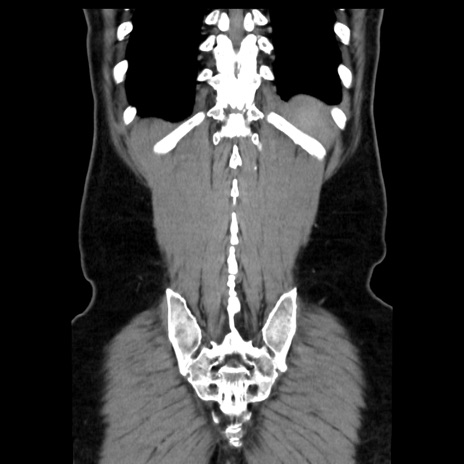

症例16(冠状断像)

【症例】 70歳代男性

【主訴】 腹痛、嘔吐

【現病歴】 約1ヶ月前より間欠的に腹痛と嘔吐あり、当院消化器内科を受診したところCTで多発する肝臓のLDAを指摘され、精査中であった。以降は消化器症状は安定していたが、2日前より嘔気と腹痛があり、同日より排便・排ガスが消失した。改善認めず、 本日、救急外来を受診した。

【身体所見】意識清明・会話良好、BT 36.3℃、BP 127/80mmHg、 P 80bpm、腹部:膨満あり、平坦・軟、上腹部正中および下腹部正中に圧痛あり、反跳痛なし、筋性防御なし。

【データ】WBC 7200、CRP 0.77